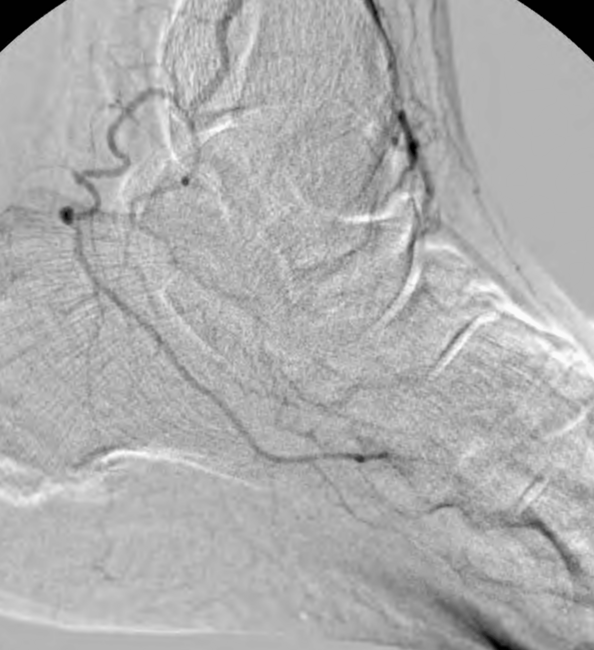

This allowed advancement of the antegrade wire (from the “up and over” access) across the occlusion in the far-distal anterior tibial artery into the dorsalis pedis artery. This was achieved carefully under extravascular ultrasound visualization. Next, completion angioplasty was performed with a 3-mm angioplasty balloon across the entirety of the distal anterior tibial artery occlusion into the patent dorsalis pedis artery (Figure 10).

The anterior tibial artery was successfully recanalized, with robust flow established into the dorsalis pedis artery (Figures 11 and 12). The patient tolerated the procedure well and did not have any complications. At 4 weeks post-intervention, the patient’s ulcer had significantly reduced in size/depth and was almost healed.